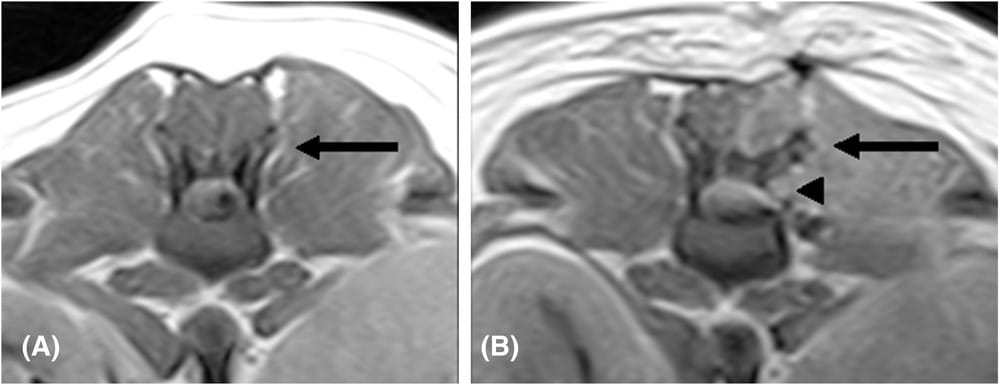

T1W transverse images of the same patient (case 17), pre-operative (A), and postoperative (B). The arrow points to the ventrally displaced left cranial articular process following left-sided mini-hemilaminectomy. A small bony defect in the left lamina of the vertebra is visible ventral to the affected articular process (arrowhead). Acquisition parameters: TR 950 (A and B) ms; TE 26 (A and B) ms; slice thickness 4 mm; slice gap 4 mm; 0.25T MRI